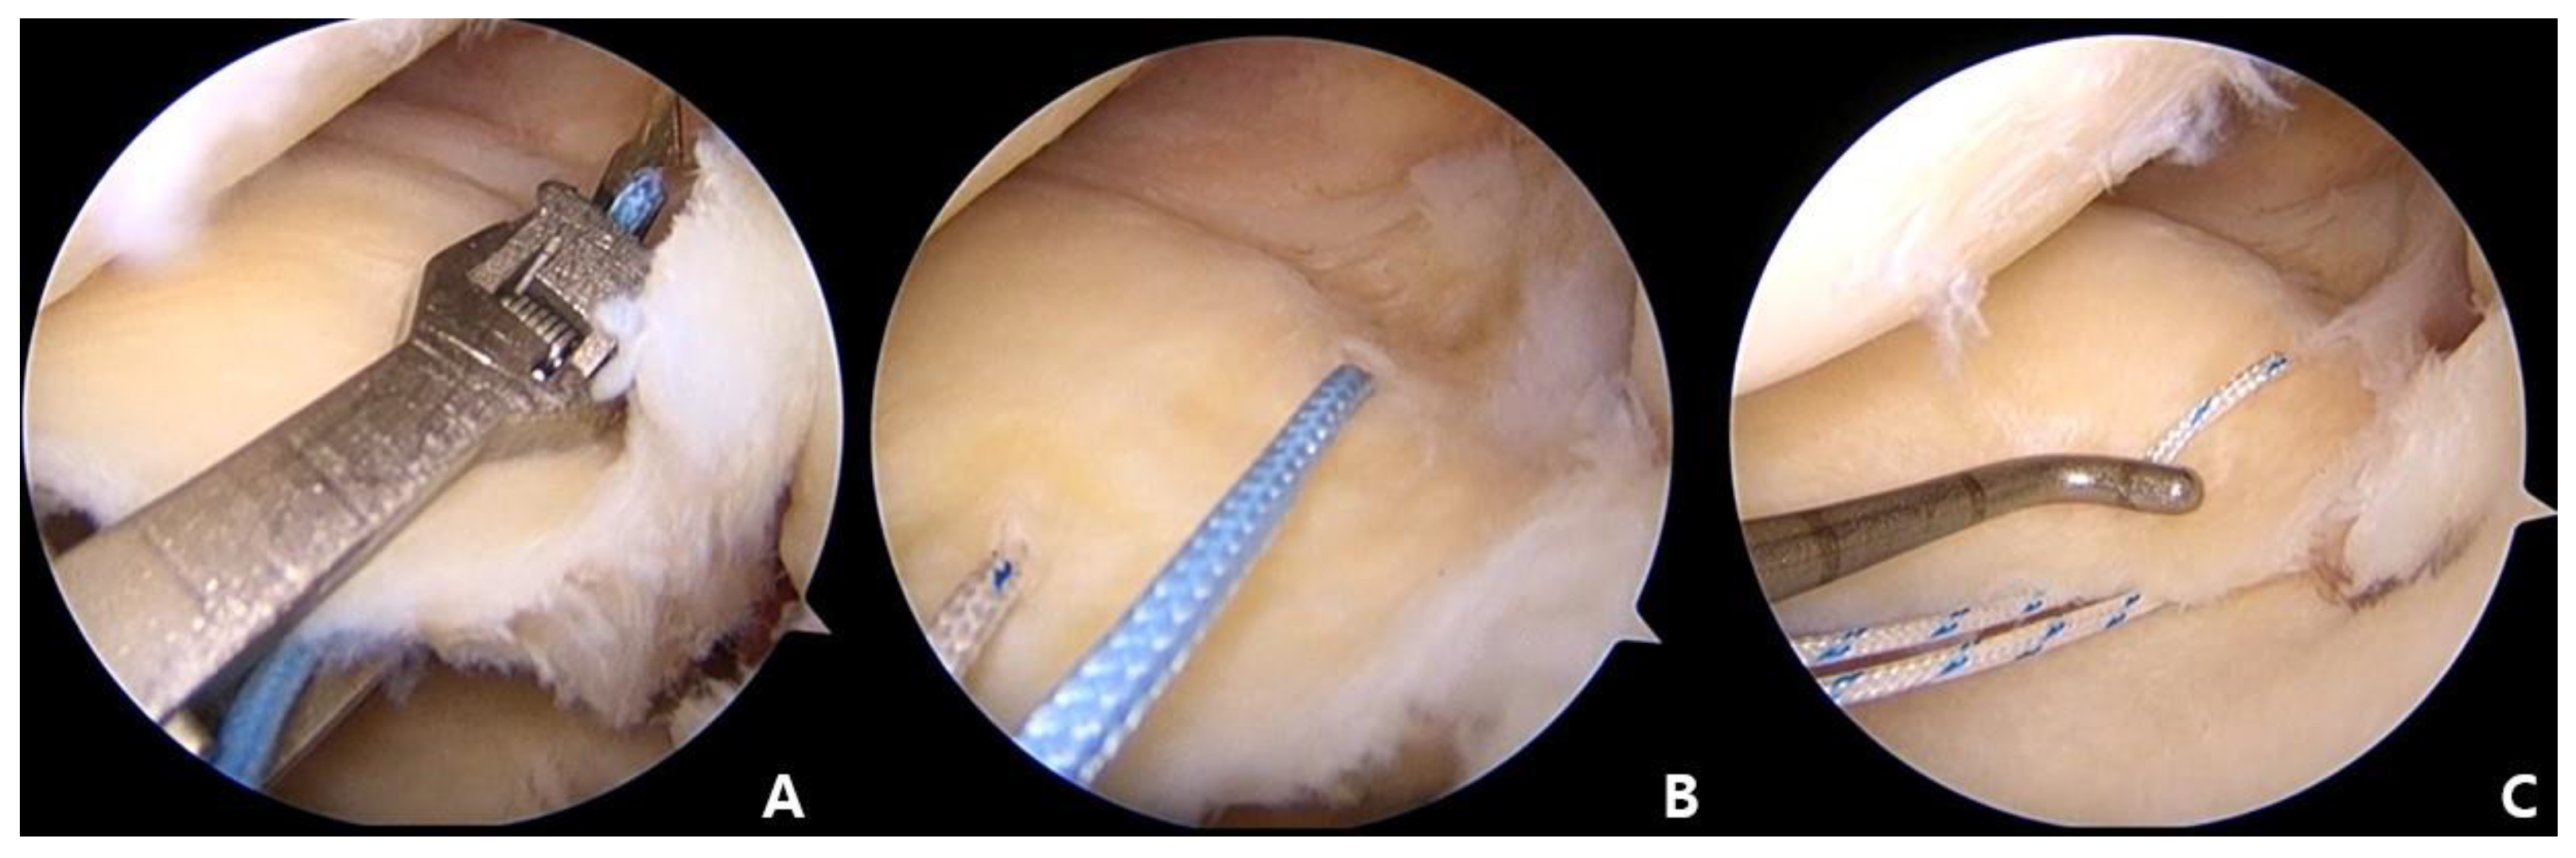

2.5. Tibial Tunnel Making

Insertion of the Meniscus Root Repair System (Smith and Nephew, Andover, MA, USA) was conducted using the AM portal. The tip of the guide was placed in the most medial side of the decorticated site of MMPR. A 2.4 mm Kirschner wire (K-wire) was advanced through the guide system. The location of the K-wire was confirmed using an arthroscope via the AL portal. The second K-wire was placed parallel and about 5 mm laterally to the first tunnel (Figure 4). Once it was verified that the position of the K-wire was acceptable, the medial-side K-wire was removed first. A metal wire was inserted into the created tunnel, and then it was withdrawn through the AM portal using an arthroscopic grasper.

2.6. Repair of MMRT

The wire was pulled through the tibial tunnel. For the medial tunnel, two horizontal stitches and two inferior vertical stitches were passed, resulting in a total of four stitches. For the lateral tunnel, the two superior vertical stitches were passed. The sutures from both tunnels were tied over the anteromedial tibial cortex, with the knee at 30° flexion. An arthroscopic re-evaluation was conducted to check for repair of the torn posterior root and to restore tension within the entire medial meniscus (Figure 5).

Figure 4. (A) Two vertical stitches overlaying and crossing the center of the horizontal suture. (B) Meniscus Root Repair System (Smith and Nephew, Andover, MA, USA) advanced using the AM portal, with the tip of the guide placed in the most medial side of the decorticated site of MMPR. (C) The second K-wire placed parallel and about 5 mm lateral to the first tunnel.

Figure 5. (A) Metal wire inserted into the tibial tunnel and pulled out through the AM portal using an arthroscopic grasper. (B) For the medial tunnel, passage of the two horizontal stitches and the two inferior vertical stitches, resulting in a total of 4 stitches. For the lateral tunnel, passage of the two superior vertical stitches. (C) An arthroscopic re-evaluation to confirm repair of the MMPH and to restore tension of the meniscus using arthroscopic probe device.